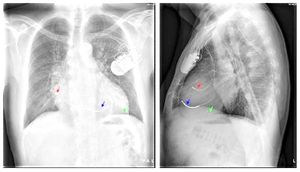

Cardiac resynchronisation therapy (CRT)

The red arrow is the right atrial lead

The blue arrow is the right ventricular lead

The green arrow is the coronary sinus lead

Implantation

CRT-P or CRT-D implantion requires implantation of three transvenous leads:

- Right atrial lead

- Right ventricular lead

- Left ventricular lead (positioned in the coronary sinus)